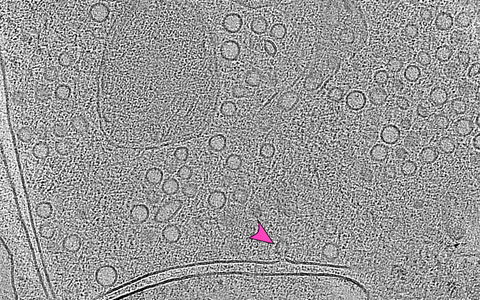

Das Bild zeigt den Moment, in dem ein Vesikel (Pfeil) mit der Zellmembran fusioniert. Durch die Überlagerung mehrerer elektronenmikroskopischer Bilder – die Elektronentomographie – wird sichtbar, wie viele Vesikel am Ende einer Nervenzelle darauf warten, ihre Botenstoffe in den synaptischen Spalt abzugeben. Dieser Zwischenraum zwischen zwei Nervenzellen ist in der Aufnahme als doppelte Linie zu erkennen.